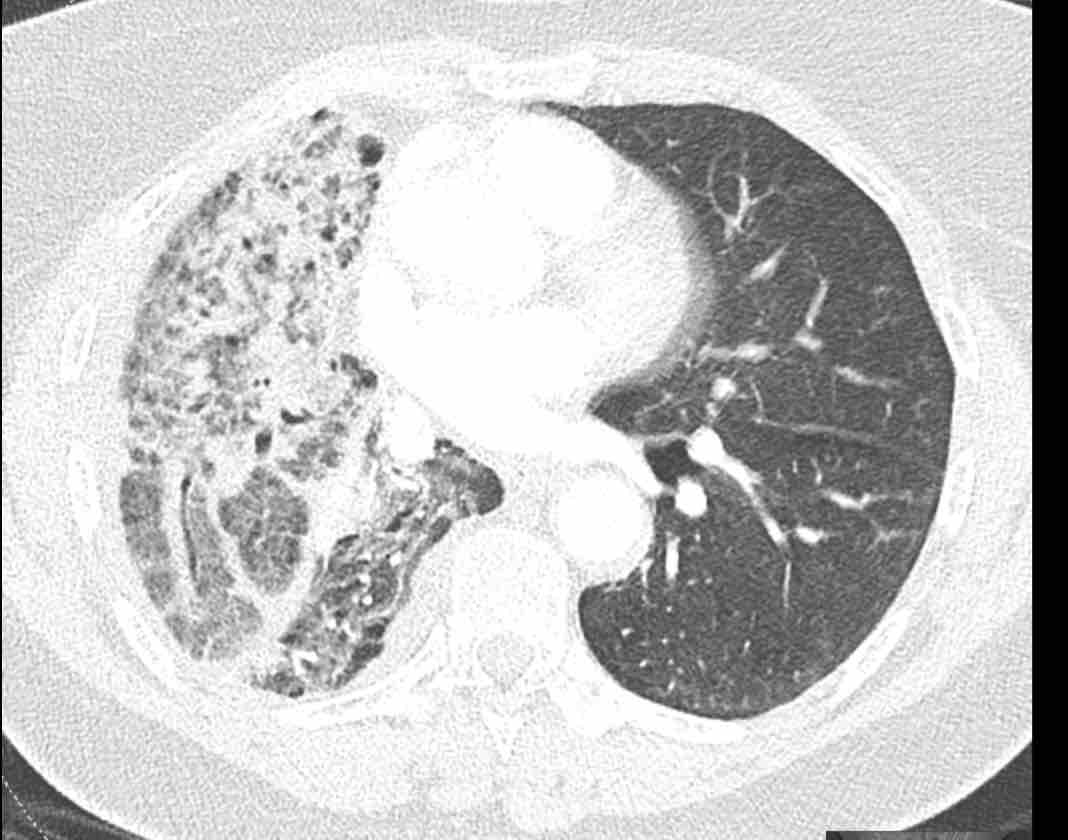

Những thay đổi cấu trúc lan rộng ở nửa ngực phải sau hóa xạ trị cho ung thư phổi không tế bào nhỏ (NSCLC) giai đoạn 4.

Theo dõi đường đi của các phế quản cho thấy thùy trên phổi phải phần lớn còn thông khí, trong khi